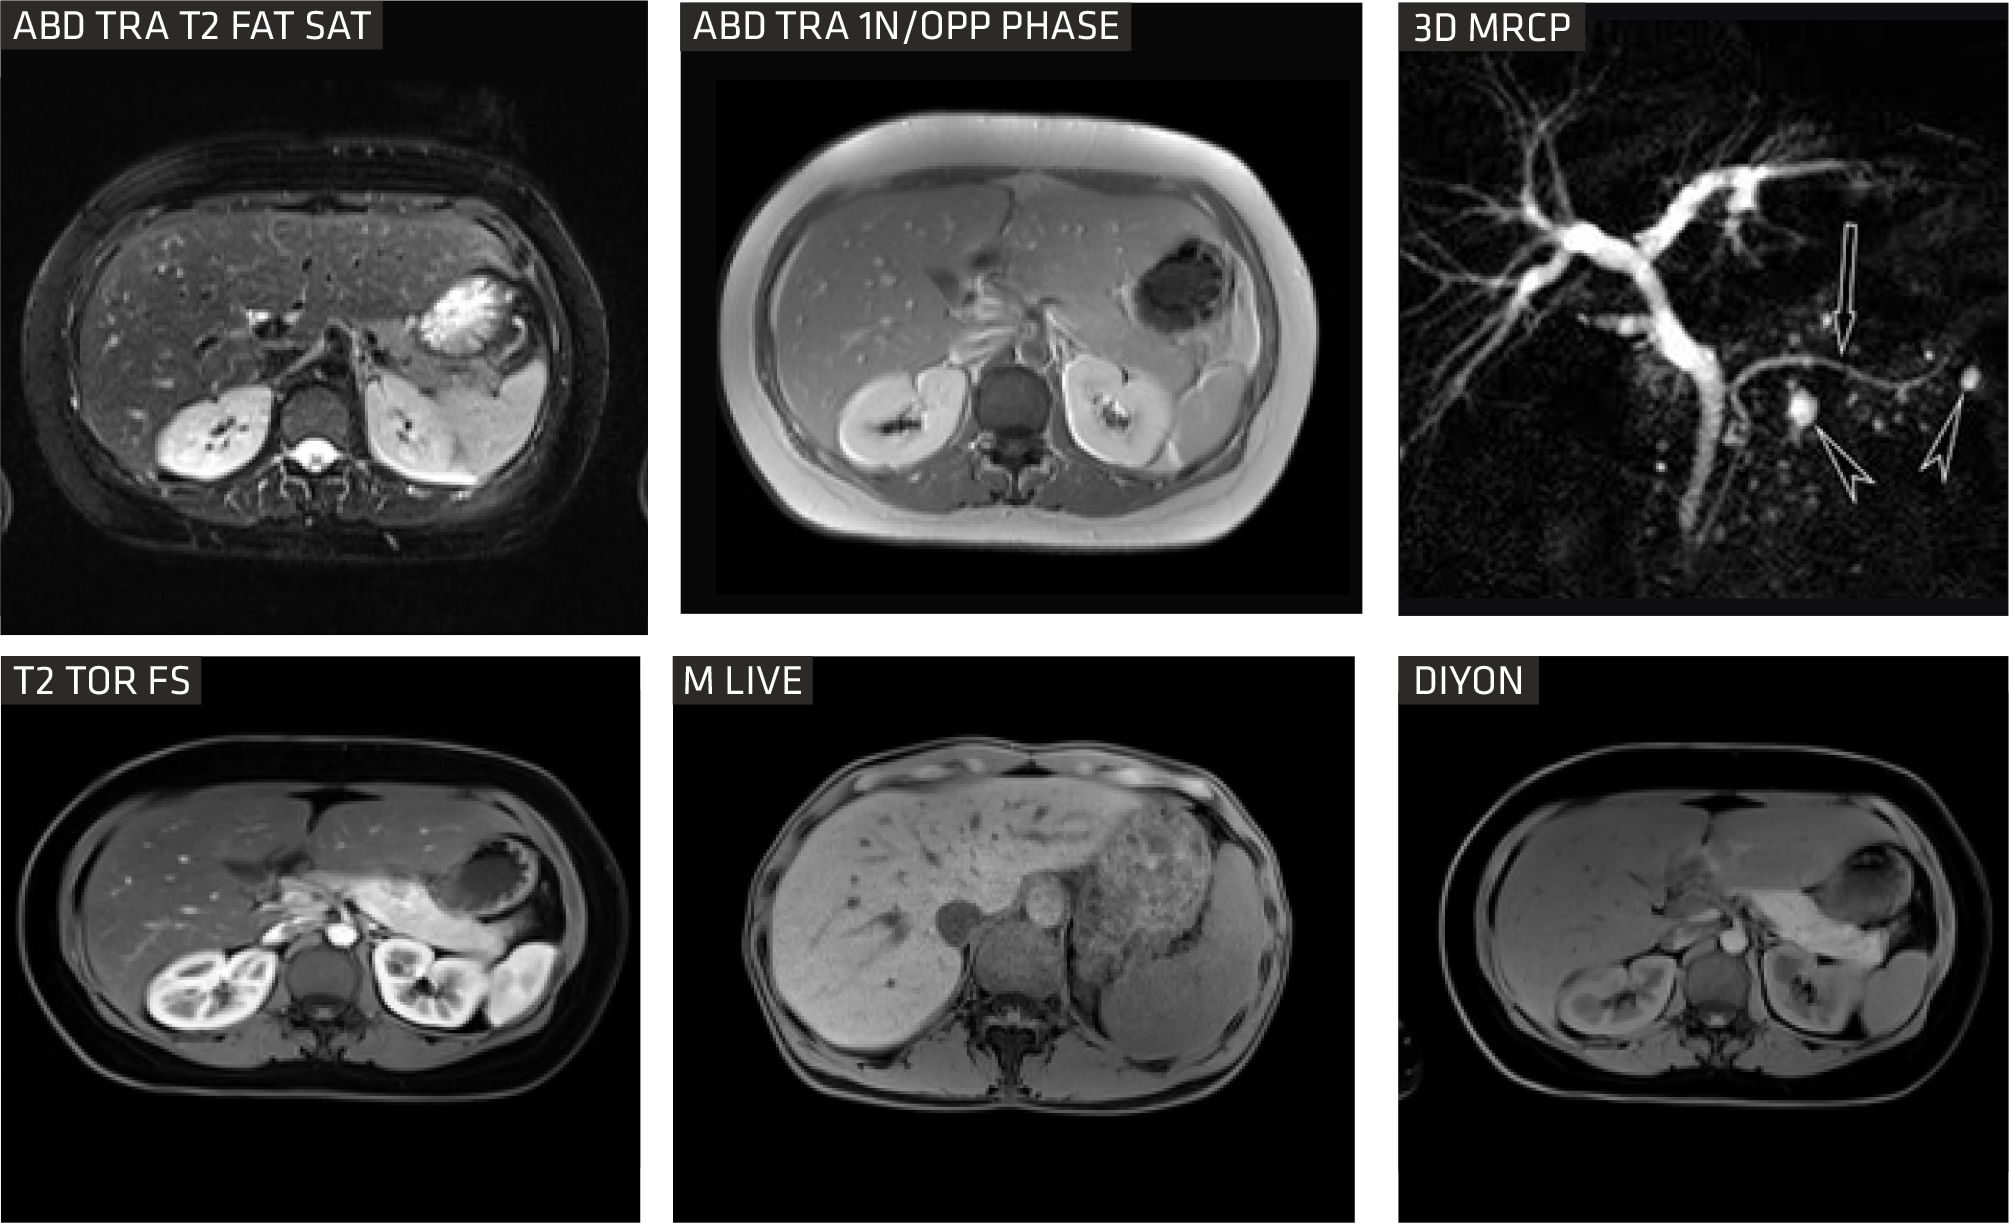

DIXON is a relatively new gradient-echo MR sequence that helps us visualize fat and water content in anatomical structures. It is reported to be useful in abdominal and brain imaging.

Advanced Body imaging

The Sequoia Healthcare Clarity 1.5T oers comprehensive body imaging solutions with advanced tools tailored for patients. Its Free Breathing (ARCUS) MR Imaging protocols primarily utilize either breath-holding techniques or respiratory gating to eectively minimize motion-related artifacts, ensuring clearer and more accurate imaging results.

mLIVE

A visualization platform is available, granting access to sophisticated postprocessing technology. Leveraging the Proton Density Fat Fraction (PDFF) method, it automatically segments and measures fat within the liver by creating quantitative fatfraction maps.